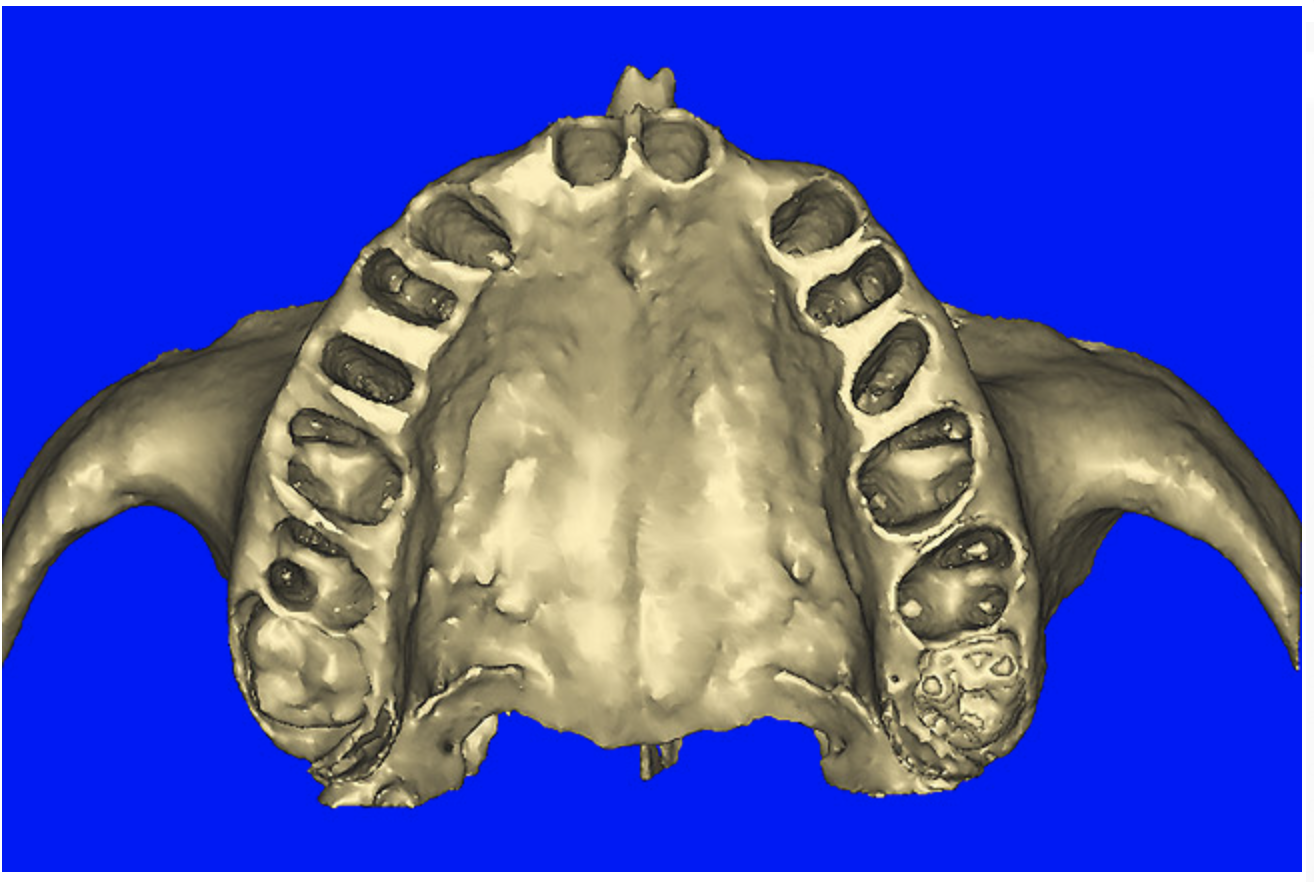

Using different masking (segmentation) and threshold Hounsfield unit values, several new 3D bone volumes can be created which offer invaluable information. To help determine the final position of each implant a new bone model was created with a Hounsfield unit value of 1480, which eliminated all but the densest objects included in the scan data. (Results may vary depending on the CBCT machine used.) The inner and outer layers of bone were removed, leaving the underlying enamel and root structure of the teeth (Figure 8A). After the bone had been stripped away, the root inclinations were examined closely. The most striking findings confirmed the rotated position of the right central, while revealing the slight mesial dilaceration of the root apex, which converged on the space needed for the path of the potential implant (Figure 8B). The schematic shapes of the proposed implants were visualized for the right and left lateral spaces in different rotations of the 3D maxillary arch. It was at this point that a determination was made as to the appropriate implant shape and type that would fit the available space while avoiding encroachment on adjacent tooth roots. A tapered design implant (Tapered Screw-Vent®, Zimmer Dental, www.zimmerdental.com) was chosen from the large virtual library. With the SIMPlant software, the virtual library contains data from dozens of implant manufacturers and realistic computer-aided design representations as seen in Figure 9A through the translucent bone. The position of the left implant can be visualized with adequate mesial-distal distance between adjacent tooth roots (Figure 9B) and a more delicate placement (Figure 9C).

Figure 12a  (A) By sectioning the 3D model, virtual implant placement was assessed for the necessary 2 mm of facial and palatal bone surrounding the implant, and (B) by using segmentation techniques to remove the existing teeth, leaving the sockets, the alveolar complex was appreciated fully.

Figure 12a

Figure 12b  (A) By sectioning the 3D model, virtual implant placement was assessed for the necessary 2 mm of facial and palatal bone surrounding the implant, and (B) by using segmentation techniques to remove the existing teeth, leaving the sockets, the alveolar complex was appreciated fully.

Figure 12b